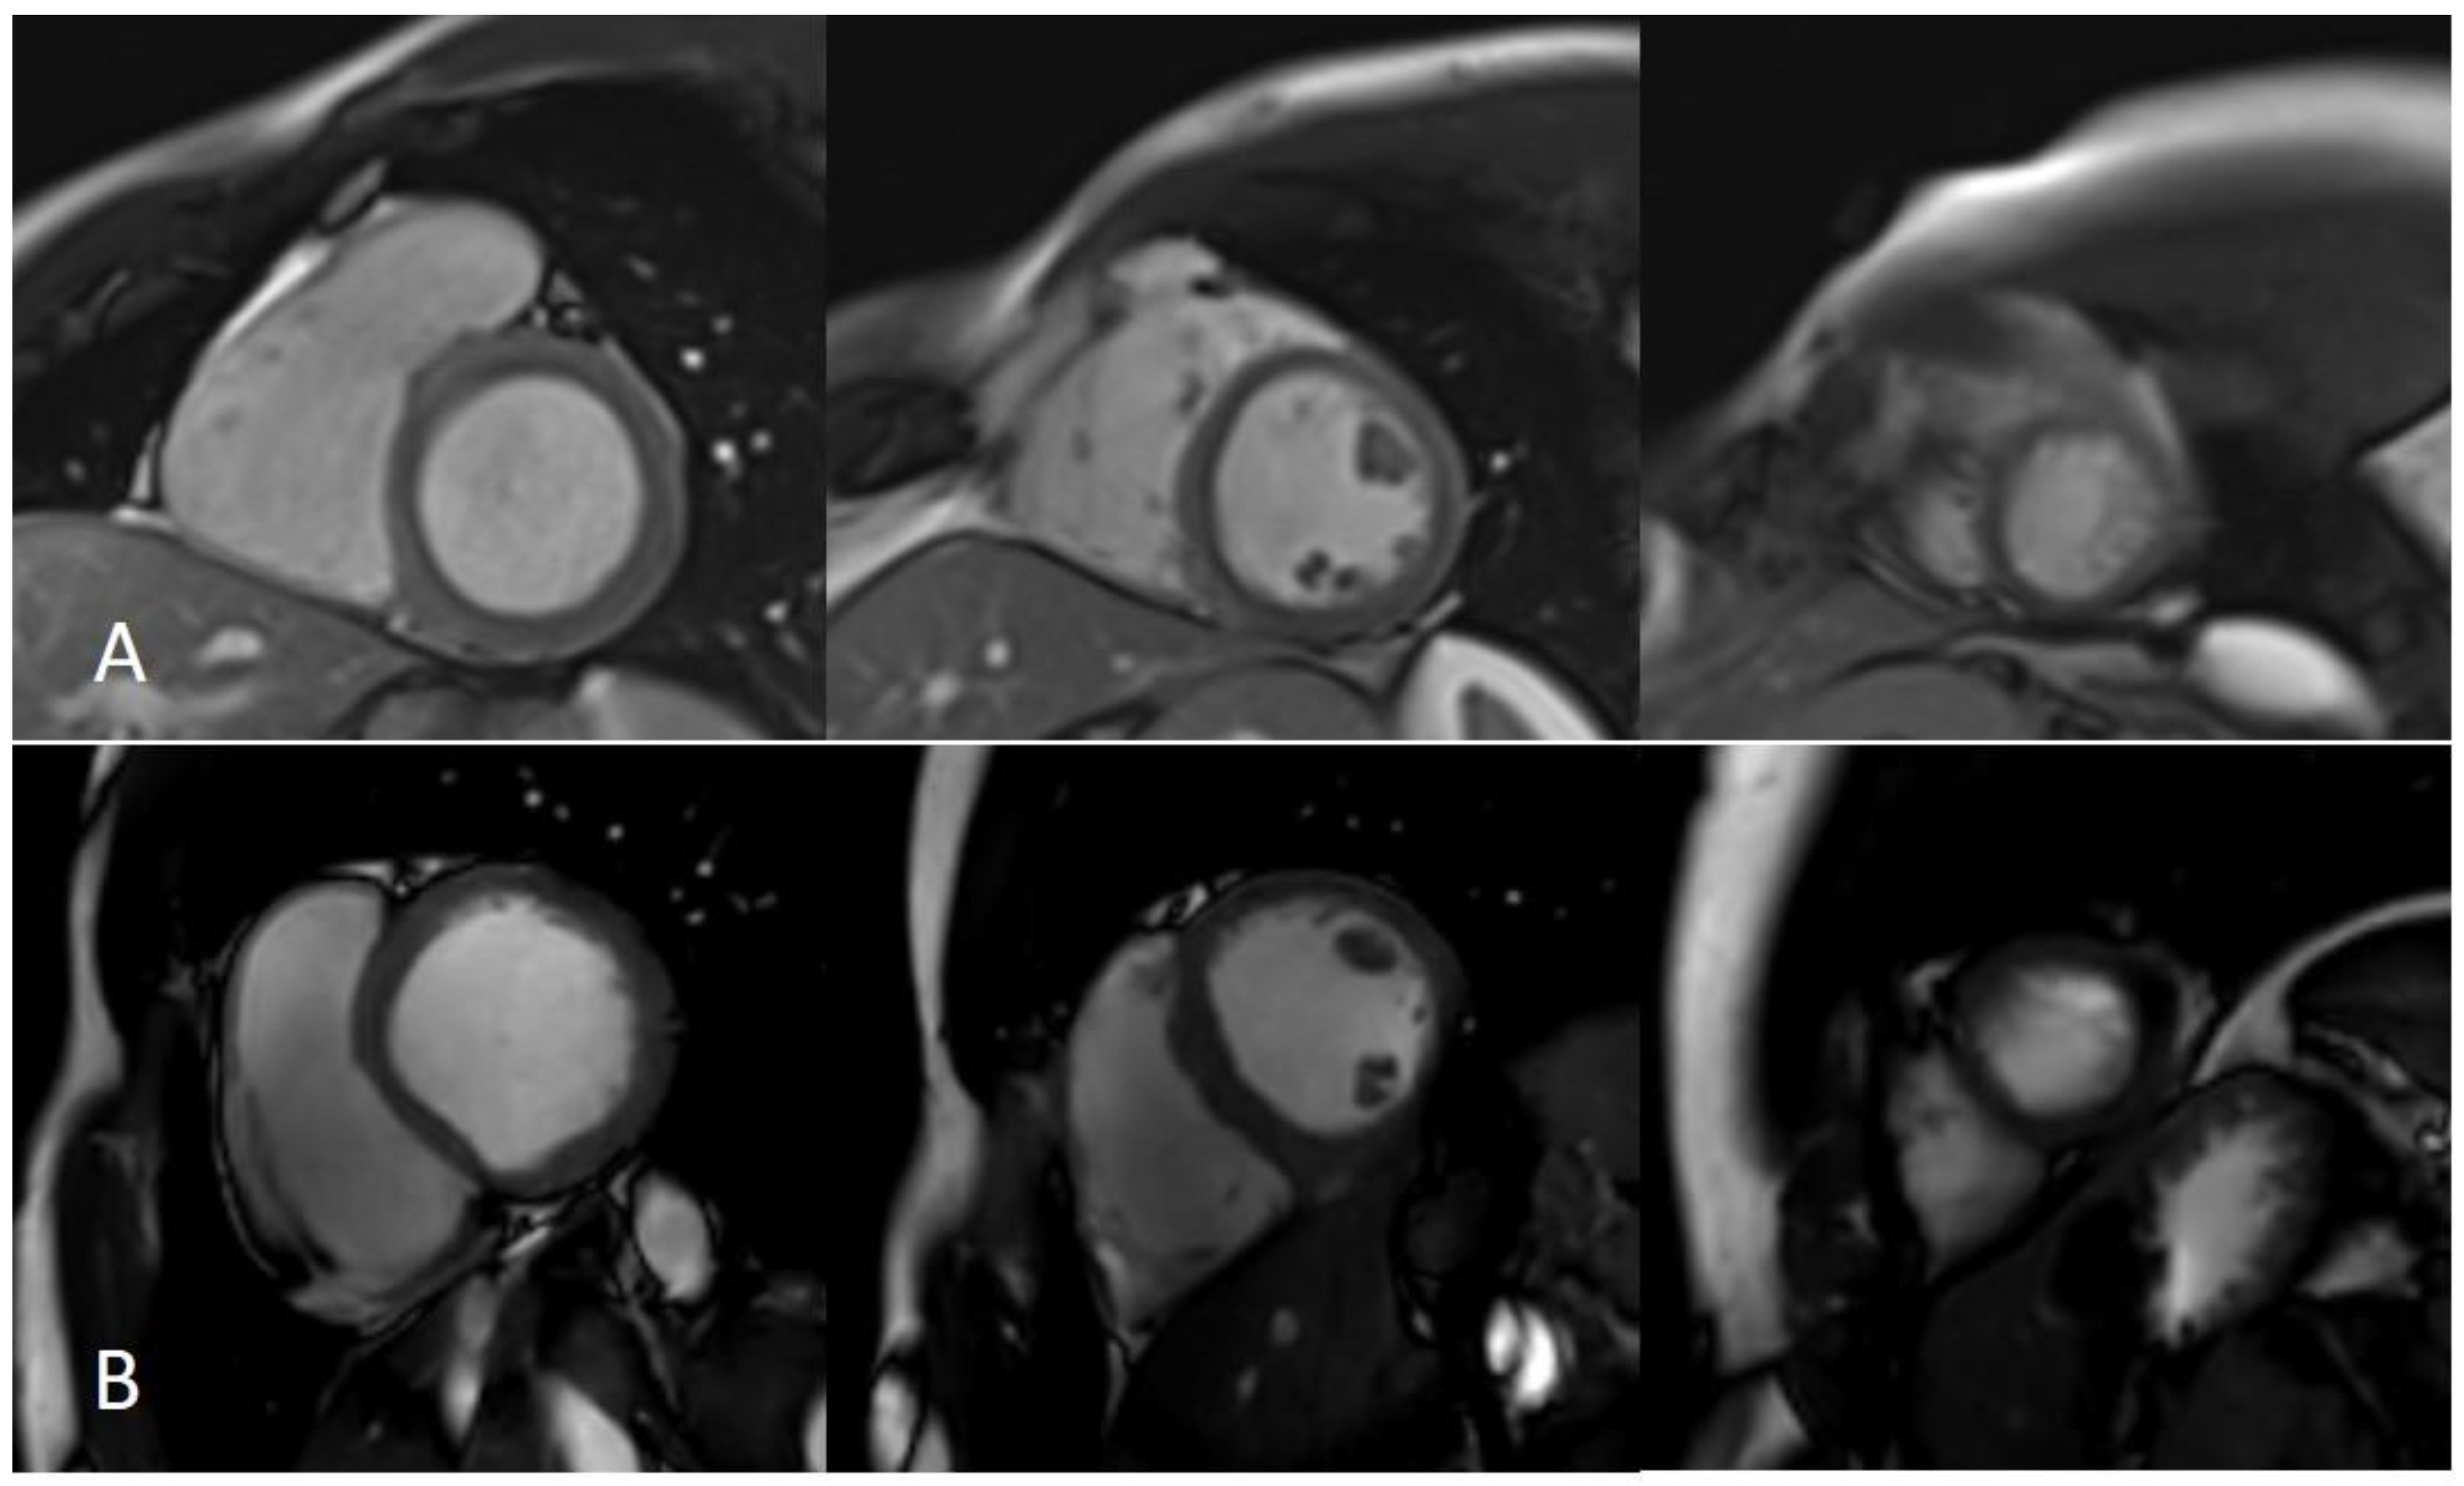

Figure 8.

Assessment of myocardial scar with semiautomatic tissue characterization. Semiautomatic tissue characterization algorithm allowing the identification of myocardial scars (represented by hyper-enhanced myocardium in panel (A) and yellow-colored myocardium in panel (B)) by positioning a region of interest within the territory of the remote/normal myocardium (dark myocardium). Green: epicardial contour; red: endocardial contour; yellow: myocardial scar; blue: normal myocardium.